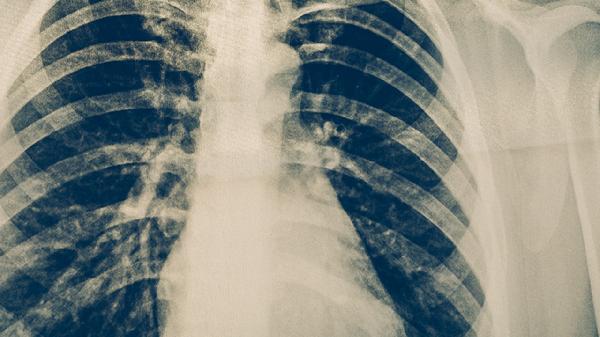

胸部X线检查是肺结核筛查的常用方法,可发现肺部异常阴影,如浸润、纤维化、钙化或空洞等病变。胸部CT检查能更清晰地显示病变的细微结构、分布特点以及与周围组织的关系,有助于发现隐匿病灶和鉴别诊断。影像学检查对肺结核的诊断和疗效评估具有重要价值。